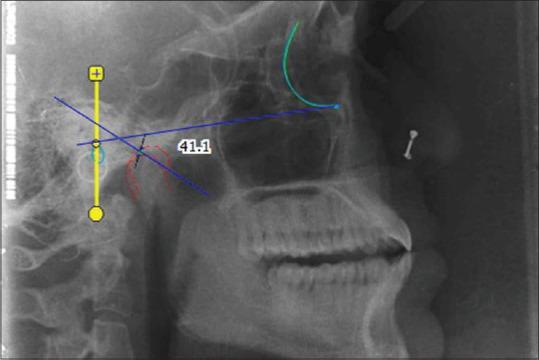

Facebow records of 25 participants were made and transferred to Hanau Wide-Vue (WV) and Hanau H2 (H2) articulators using conventional indirect transfer (CIT), superior annular groove (SAG), and inferior annular groove (IAG) as anterior reference points. Maxillary casts were mounted on each articulator followed by mandibular mountings. Protrusive interocclusal record was used to determine HCG, and SIOP was measured as an angle between the occlusal plane of mounted maxillary cast and upper member of the articulator. Both, HCG and SIOP were measured on a digital lateral cephalogram and the values obtained were compared with previously determined values from both the articulators. Intergroup comparison was done by analysis of variance and pair-wise comparison by Tukey test.

对25名参与者进行面弓记录,并使用传统间接转移(CIT)、上环形凹槽(SAG)和下环形凹槽(IAG)作为前参考点,将其转移到Hanau Wide-Vue(WV)和Hanau H2(H2)牙合架上。将上颌模型安装在每个牙合架上,随后进行下颌安装。前伸牙合记录用于确定HCG,SIOP作为安装的上颌模型牙合平面与牙合架上部件之间的角度进行测量。在数字化侧位头影测量片上测量HCG和SIOP,并将获得的值与先前从两个牙合架确定的值进行比较。组间比较采用方差分析,两两比较采用Tukey检验。